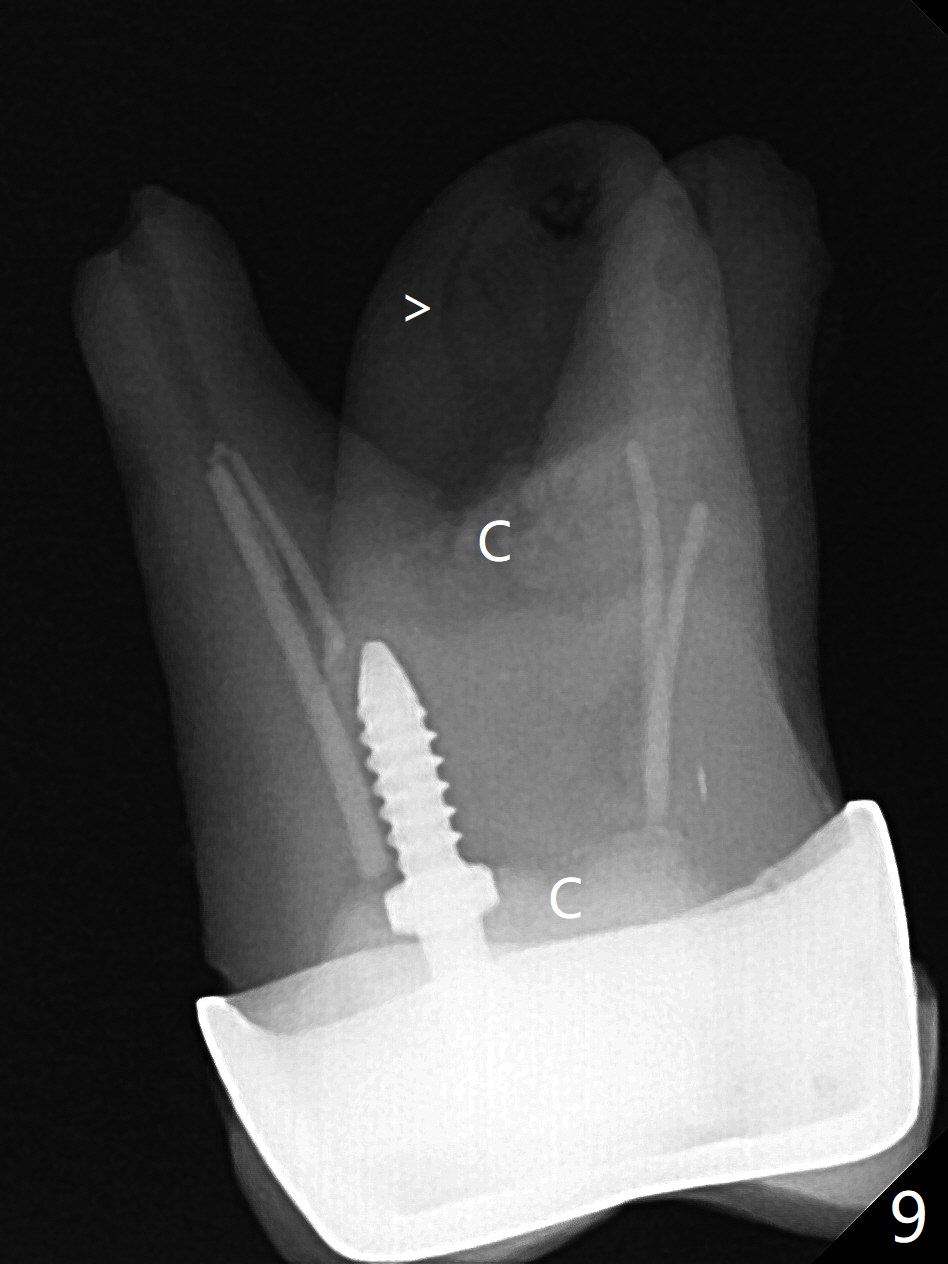

A 29-year-old man has pain in the upper left quadrant. It appears that the tooth #14 has endo and post failure with palatal fistula (Fig.1,2). The septum is almost non-existent; the palatal wall is low, while the sinus floor is present. Sticky bone is placed first against the defective palatal wall and presumably pushed as high as to the sinus floor (Fig.3-5). PRF plug/membrane and 6-month membrane are used to close the socket with 4-0 Chromic gut suture apparently securely, followed by periodontal dressing. Examination of the extracted tooth shows granulation tissue between the roots (Fig.6 *). Underneath the granulation tissue is cement-like material (Fig.7 C). Distal-to-mesial X-ray examination shows possible furcation perforation (Fig.8 *), while mesial-to-distal one the cement-like material in the furca and pulpal chamber as well as MB2 (Fig.9 >). The patient returns 8 days postop, reporting pain reduction, but wants to have #16 extracted. The periodontal dressing is loose, but stuck with 2 sutures underneath. When the dressing is removed, the wound looks normal (Fig.10). In fact the dressing is re-applied. The 6-month membrane has lost 1 month postop. The majority of the socket heals except the palatal (Fig.11 *), as related to the existing palatal fistula/defect (^). Orthodontics is being considered. If the buccal plate collapses 4.5 months post extraction, socket shield should have been done. In fact the buccal plate is robotic, while the bone density is low palatal in CT (Fig.12).